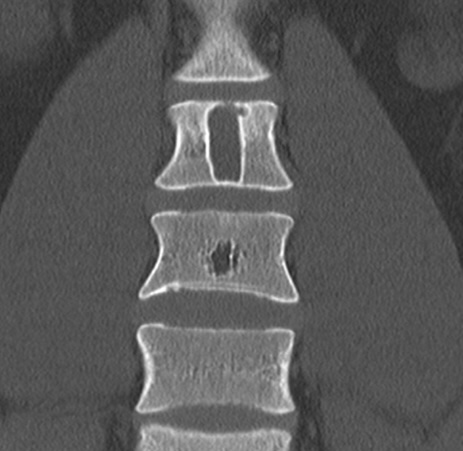

Костные кисты

- Локализуются преимущественно в телах позвонков или дугах, имеют чёткие и иногда вздутые контуры.

- Аневризматическая киста — многокамерное образование с тонкими септами и возможными уровнями жидкости, сигнал — гетерогенный.

- Солитарная киста — однокамерная, содержимое однородное, плотность 10–30 HU, без перегородок и кальцинатов.

- Могут сопровождаться истончением и выбуханием кортикального слоя.

- В ряде случаев отмечаются признаки компрессии канала или нестабильности позвонков.